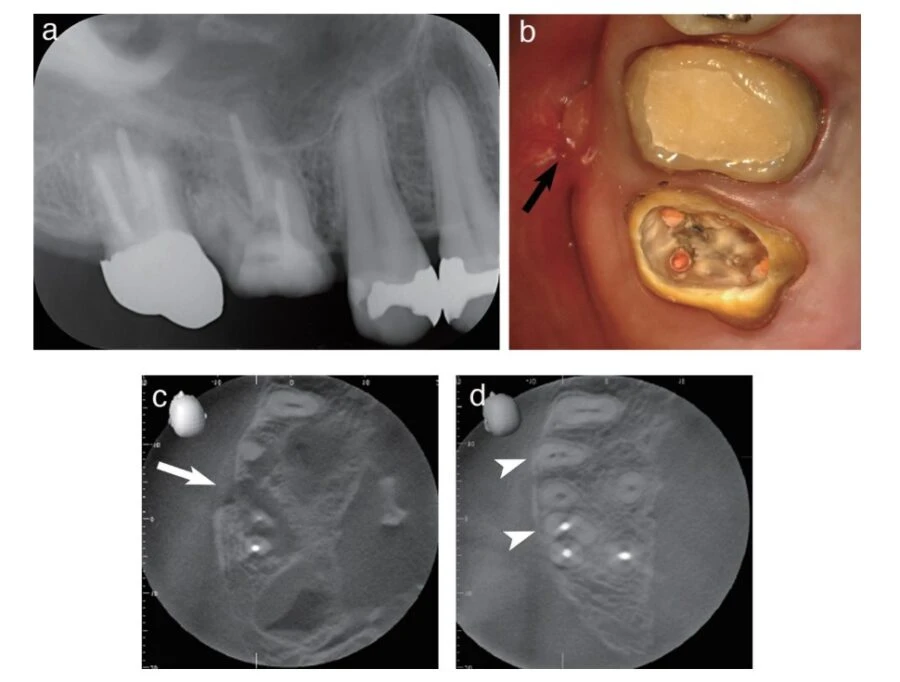

Một bệnh nhân 40 tuổi được sử dụng vật liệu trám bít ống tủy BG Multi chứa thủy tinh sinh học trong quá trình trám bít.

Hình ảnh X-quang được chụp trong quá trình điều trị trước khi điều trị nội nha cho thấy thấu quang rõ ràng ở khu vực quanh chân răng của răng nanh bên trái hàm trên; độ trong mờ trên phim chụp X quang này được chẩn đoán là viêm quanh chóp có triệu chứng. (Hình a)

Sau khi điều trị nội nha tiêu chuẩn, ống tủy được trám bít bằng vật liệu trám bít ống tủy BG Multi và gutta-percha bằng kỹ thuật không lèn. (Hình b)

Quá trình lành vết thương và hình thành xương của mô quanh chóp được quan sát thấy sau 6 tháng và 14 tháng sau khi trám bít. (Hình c và d)

Kết luận: Chất trám bít ống tủy BG Multi đã được chứng minh là có khả năng đẩy nhanh quá trình lành thương và tái tạo mô quanh chóp trong các trường hợp lâm sàng.